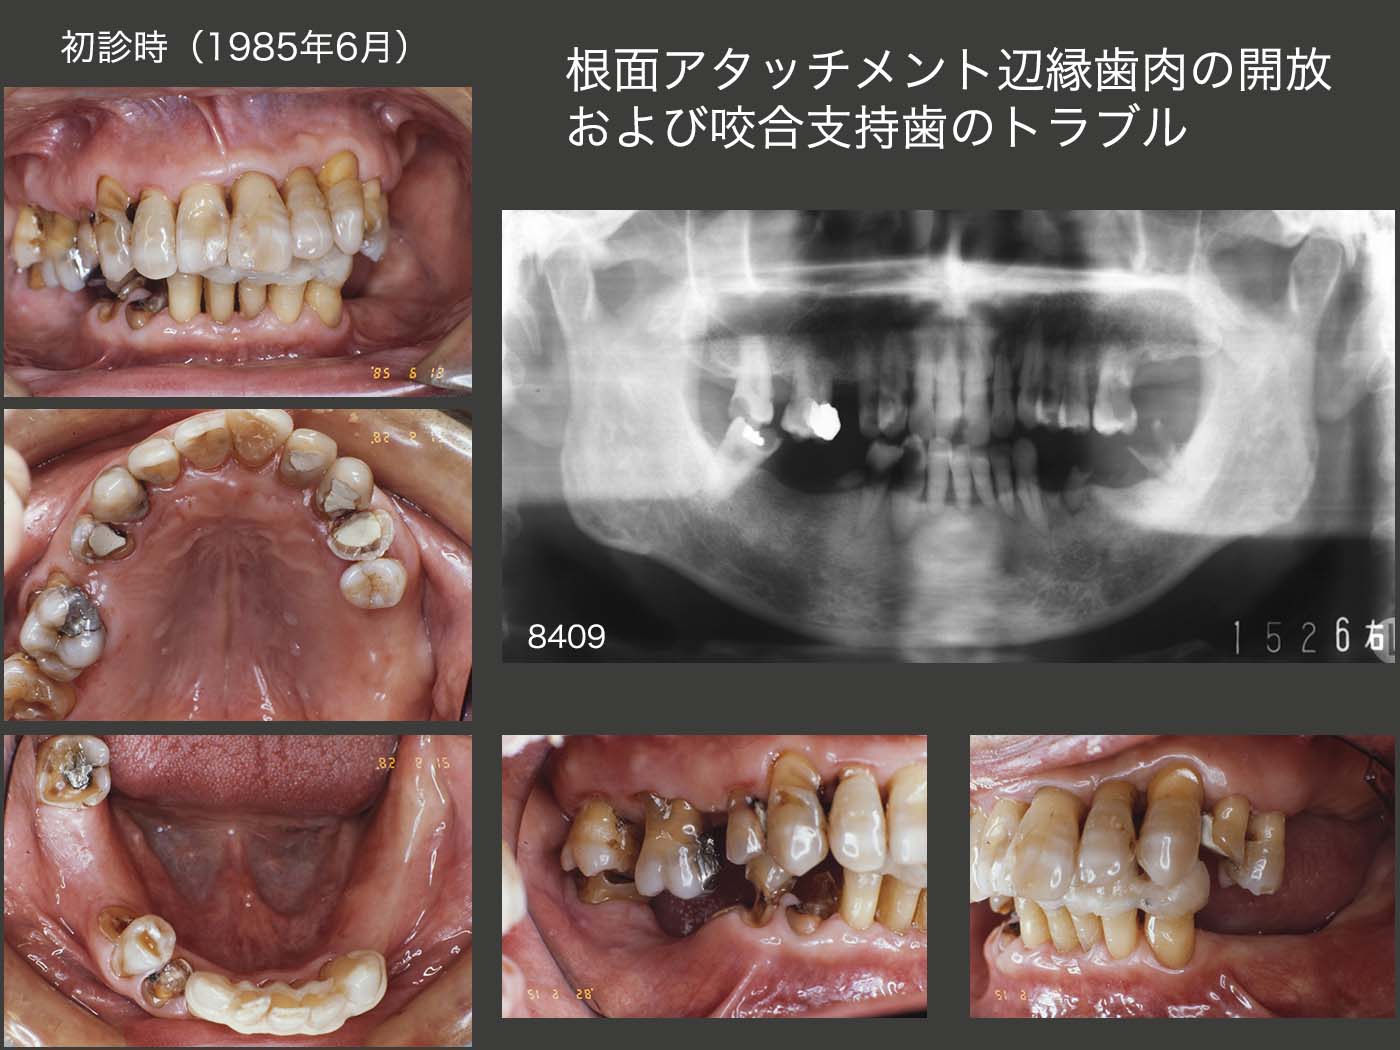

26.根面アタッチメント辺縁歯肉の開放および咬合支持歯のトラブル

初診は1985年6月,59歳男性.東京歯科大学病院時代の症例であり,保存科にて,抜歯,抜髄等がなされ,補綴処置を私が引き継ぐことになった.パノラマX線写真は,84年9月,保存科受診時の状態である.臼歯部の咬合支持歯は2個所であるが,右下4は何時歯冠破折するか分からない状況なので,咬耗は大きいながら,しっかり咬合している右側の上下7がこの症例のキイ・ティースである.

義歯装着の経験はなく,どうしても前歯で食事をとっているため,下顎前歯の歯周病が進行していた.本来なら総合的な一口腔単位の観点から,まず下顎に暫間義歯を装着し,下顎位を確保してから保存処置を行うべきであるが,この当時大学病院においてはこのような考え方あるいはシステムはなく,科別診療が行われていた.私自身もまだ卒後5年目,大学院を修了した年であり,全く臨床の基本が分かっていなかった.特に,咬合支持という概念は全くなく,また今であったら絶対にあり得ない右上3,6,7,右下7,左下2,3の抜随を再度保存科に依頼してしまったことは,痛恨のミスである.なお,この間も義歯は製作せず,あくまでも保存科での処置が終わってから,補綴するという考えに固着していた.